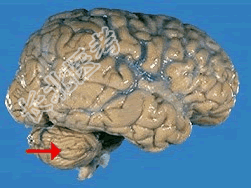

- 单项选择题如图箭头所示,应属于大脑的哪个部位 ( )

A、脑干

B、额叶

C、枕叶

D、小脑

E、顶叶